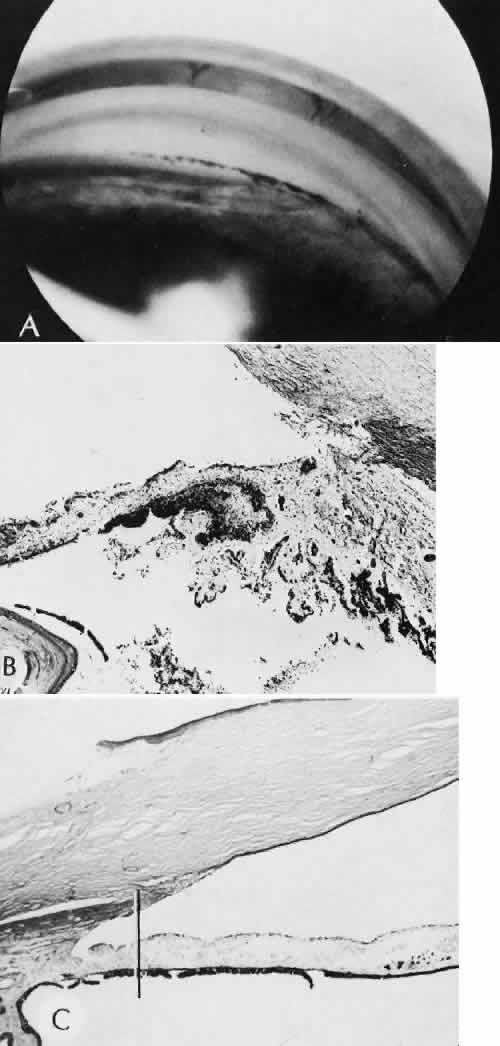

Cyclocryotherapy, cyclodiathermy (Fig. 20), and therapeutic ultrasonography apply energy directly to the pars plicata and cause lysis of the ciliary muscle and occlusion of the vascular supply, leading to extensive necrosis and scarring. Pressure lowering is accomplished by a reduction of aqueous production. Heat applied to the sclera may cause necrosis and localized scleral thinning. Cold applied to the sclera, unless extreme, does not cause any clinical or histologic changes.

Fig. 20. Cyclodiathermy treatment of the ciliary body to control glaucoma. A. Gross photograph illustrates extensive areas of depigmentation mainly in the region of the pars plana (arrows) rather than the pars plicata. B. Light micrograph of the region of the pars plana illustrates an extensive area of tissue degeneration of the pars plana (between arrows) in the late postoperative course. C. Light micrograph of the destructive effects of cyclocryotherapy also in the region of the pars plana and pars plicata. The ciliary epithelium in the early postoperative period is necrotic and cystic. (Hematoxin-eosin stain; A, × 8; B, × 16.)